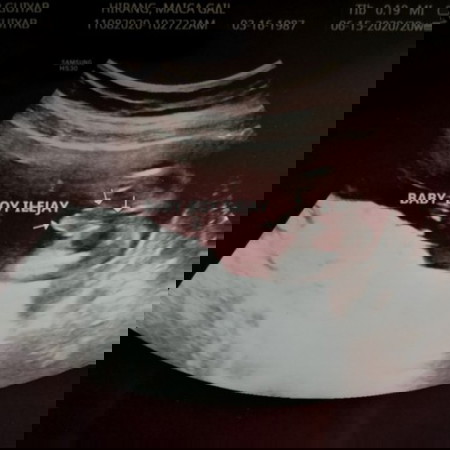

We can't wait to meet you, our baby boy! ❤️ I've been praying na maging okay lahat sa CAS natin and sobrang thankful ako dahil normal and okay naman lahat. Ang likot likod mo pa kaya tuwang tuwa si doc. Palakas pa tayo lalo anak ha. Ang daming nagppray para sayo. 🙏 🙏 🙏 Mahal na mahal ka namin, anak! ❤️❤️❤️ #firstbaby #pregnancy #1stimemom